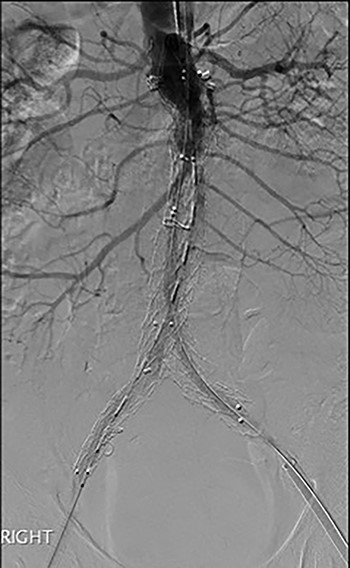

Post-EVAR angiogram showing acute thrombosis of the right limb and subtotal thrombosis of the left limb and trunk.

An angiogram at this stage demonstrated acute thrombosis of the right limb, and subtotal thrombosis of the left limb (Fig. 2). A further bolus of 2000 units Heparin was given intravenously. Thrombectomy was performed by advancing the 16Fr Sentrant sheaths into the limbs of the endograft followed by retraction under negative pressure. This manoeuvre restored antegrade arterial flow on both sides although there was a large volume of acute thrombus within the limbs of the endograft. A decision was made to perform intra-arterial thrombolysis. The 16Fr Sentrant sheath was removed from the left common femoral artery and haemostasis secured with the Proglides. The right-sided 16Fr sheath was downsized to 8 Fr sheath (the Proglide sutures were tightened around this sheath, achieving haemostasis around the smaller sheath). A multi-side hole straight angiographic catheter was placed in the body of the endograft for the thrombolysis. A bolus of 5 mg Actilyse (Boehringer Ingelheim, Ingelheim am Rhein, Germany) was given through this followed by a 1 mg/h infusion. An IV heparin infusion was started at 1000 units/h through the side arm of the 8 Fr sheath.

The patient was transferred to the high-dependency unit for observation during the thrombolysis. After 4-h, the patient was taken back to Interventional Radiology department for a check angiogram (Fig. 3). This demonstrated a fully re-canalized aorto-iliac system with no distal thrombotic or embolic complications. The thrombolysis infusion was stopped at this stage. In the post-operative period, anticoagulation has been continued with Apixaban. A CT scan 6 weeks post-procedure has confirmed ongoing patency of the endograft with no visible thrombus (Fig. 4).